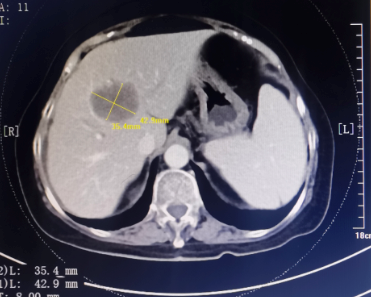

患者为67岁女性,1年余前诊断胃腺癌晚期,肝脏、骨骼及淋巴结多发转移,本次入院复查发现肝脏病灶进展,科主任白俊主任医师、主管医生刘莹主治医师详细分析并与患者家属沟通病情,考虑患者既往接受多线系统性抗肿瘤药物治疗,且治疗过程中多次出现剂量限制性骨髓毒性,继续更换药物治疗的选择空间不多,推荐超声引导下微波消融部分肝脏转移病灶,以期为后续继续免疫及靶向治疗创造在体瘤苗的机会。段宝军副主任医师认真阅片后,考虑该例患者肝转移病灶大(最大径超过5厘米),且毗邻膈肌、肝左静脉及第一肝门等重要结构,因此采用3D可视化手术规划系统设计微波消融方案,在麻醉科常建华副主任医师及手术室的精心配合下,顺利完成了肝转移病灶微波消融手术。

超声引导下肝癌病灶微波消融术微创、经济,且无辐射,是指南推荐的肝癌标准治疗方案。但由于重复进针的人为误差、热传导不足、肝脏储备功能等因素的影响,大肝癌的消融治疗难以做到根治性消融,尤其是危险区域的肝癌病灶微波消融易发生严重并发症,导致超声引导下微波消融的治疗作用与外科手术存在一定差距。